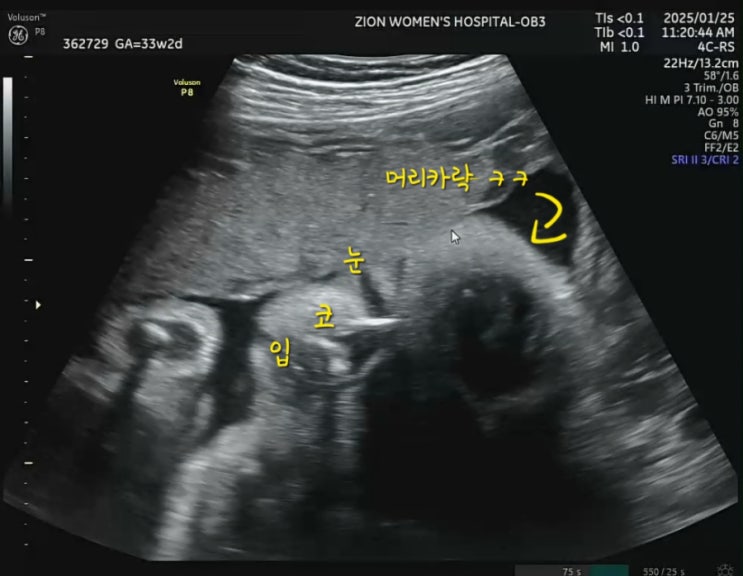

[임신33주] 유모차구입 / 세탁기청소 / 태아몸무게 / D-50

임신 32주 32주가 임신 9개월이라구요..??! 예정일까지 8주 남았는데 9개월이라니..?? 이해는 잘 안되지만....